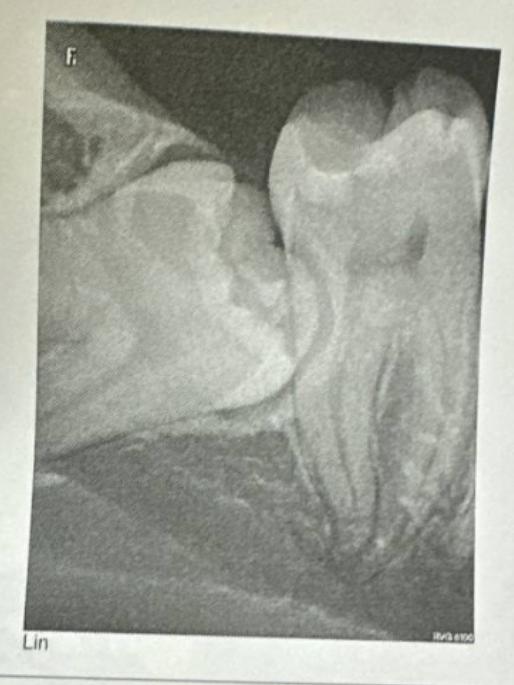

Так в начале декабря 2024 года я пришла на очередной осмотр и решила пожаловаться врачу на периодическую боль в нижних правых зубах сзади, меня направили на рентген этих зубов. На снимке я увидела лежачий зуб мудрости и поняла, что это серьёзно — меня настигла проблема, про которую я даже не задумывалась — зубы мудрости… Оказалось, что у меня ретинированный, то есть не прорезавшийся зуб мудрости.

Меня направили к стоматологу-хирургу, он сказал, что около корней этого зуба проходит нерв, это сложный случай и скорее всего надо будет делать операцию по удалению этого зуба мудрости, выдал направление в ГКБ №1 им. Н. И. Пирогова.